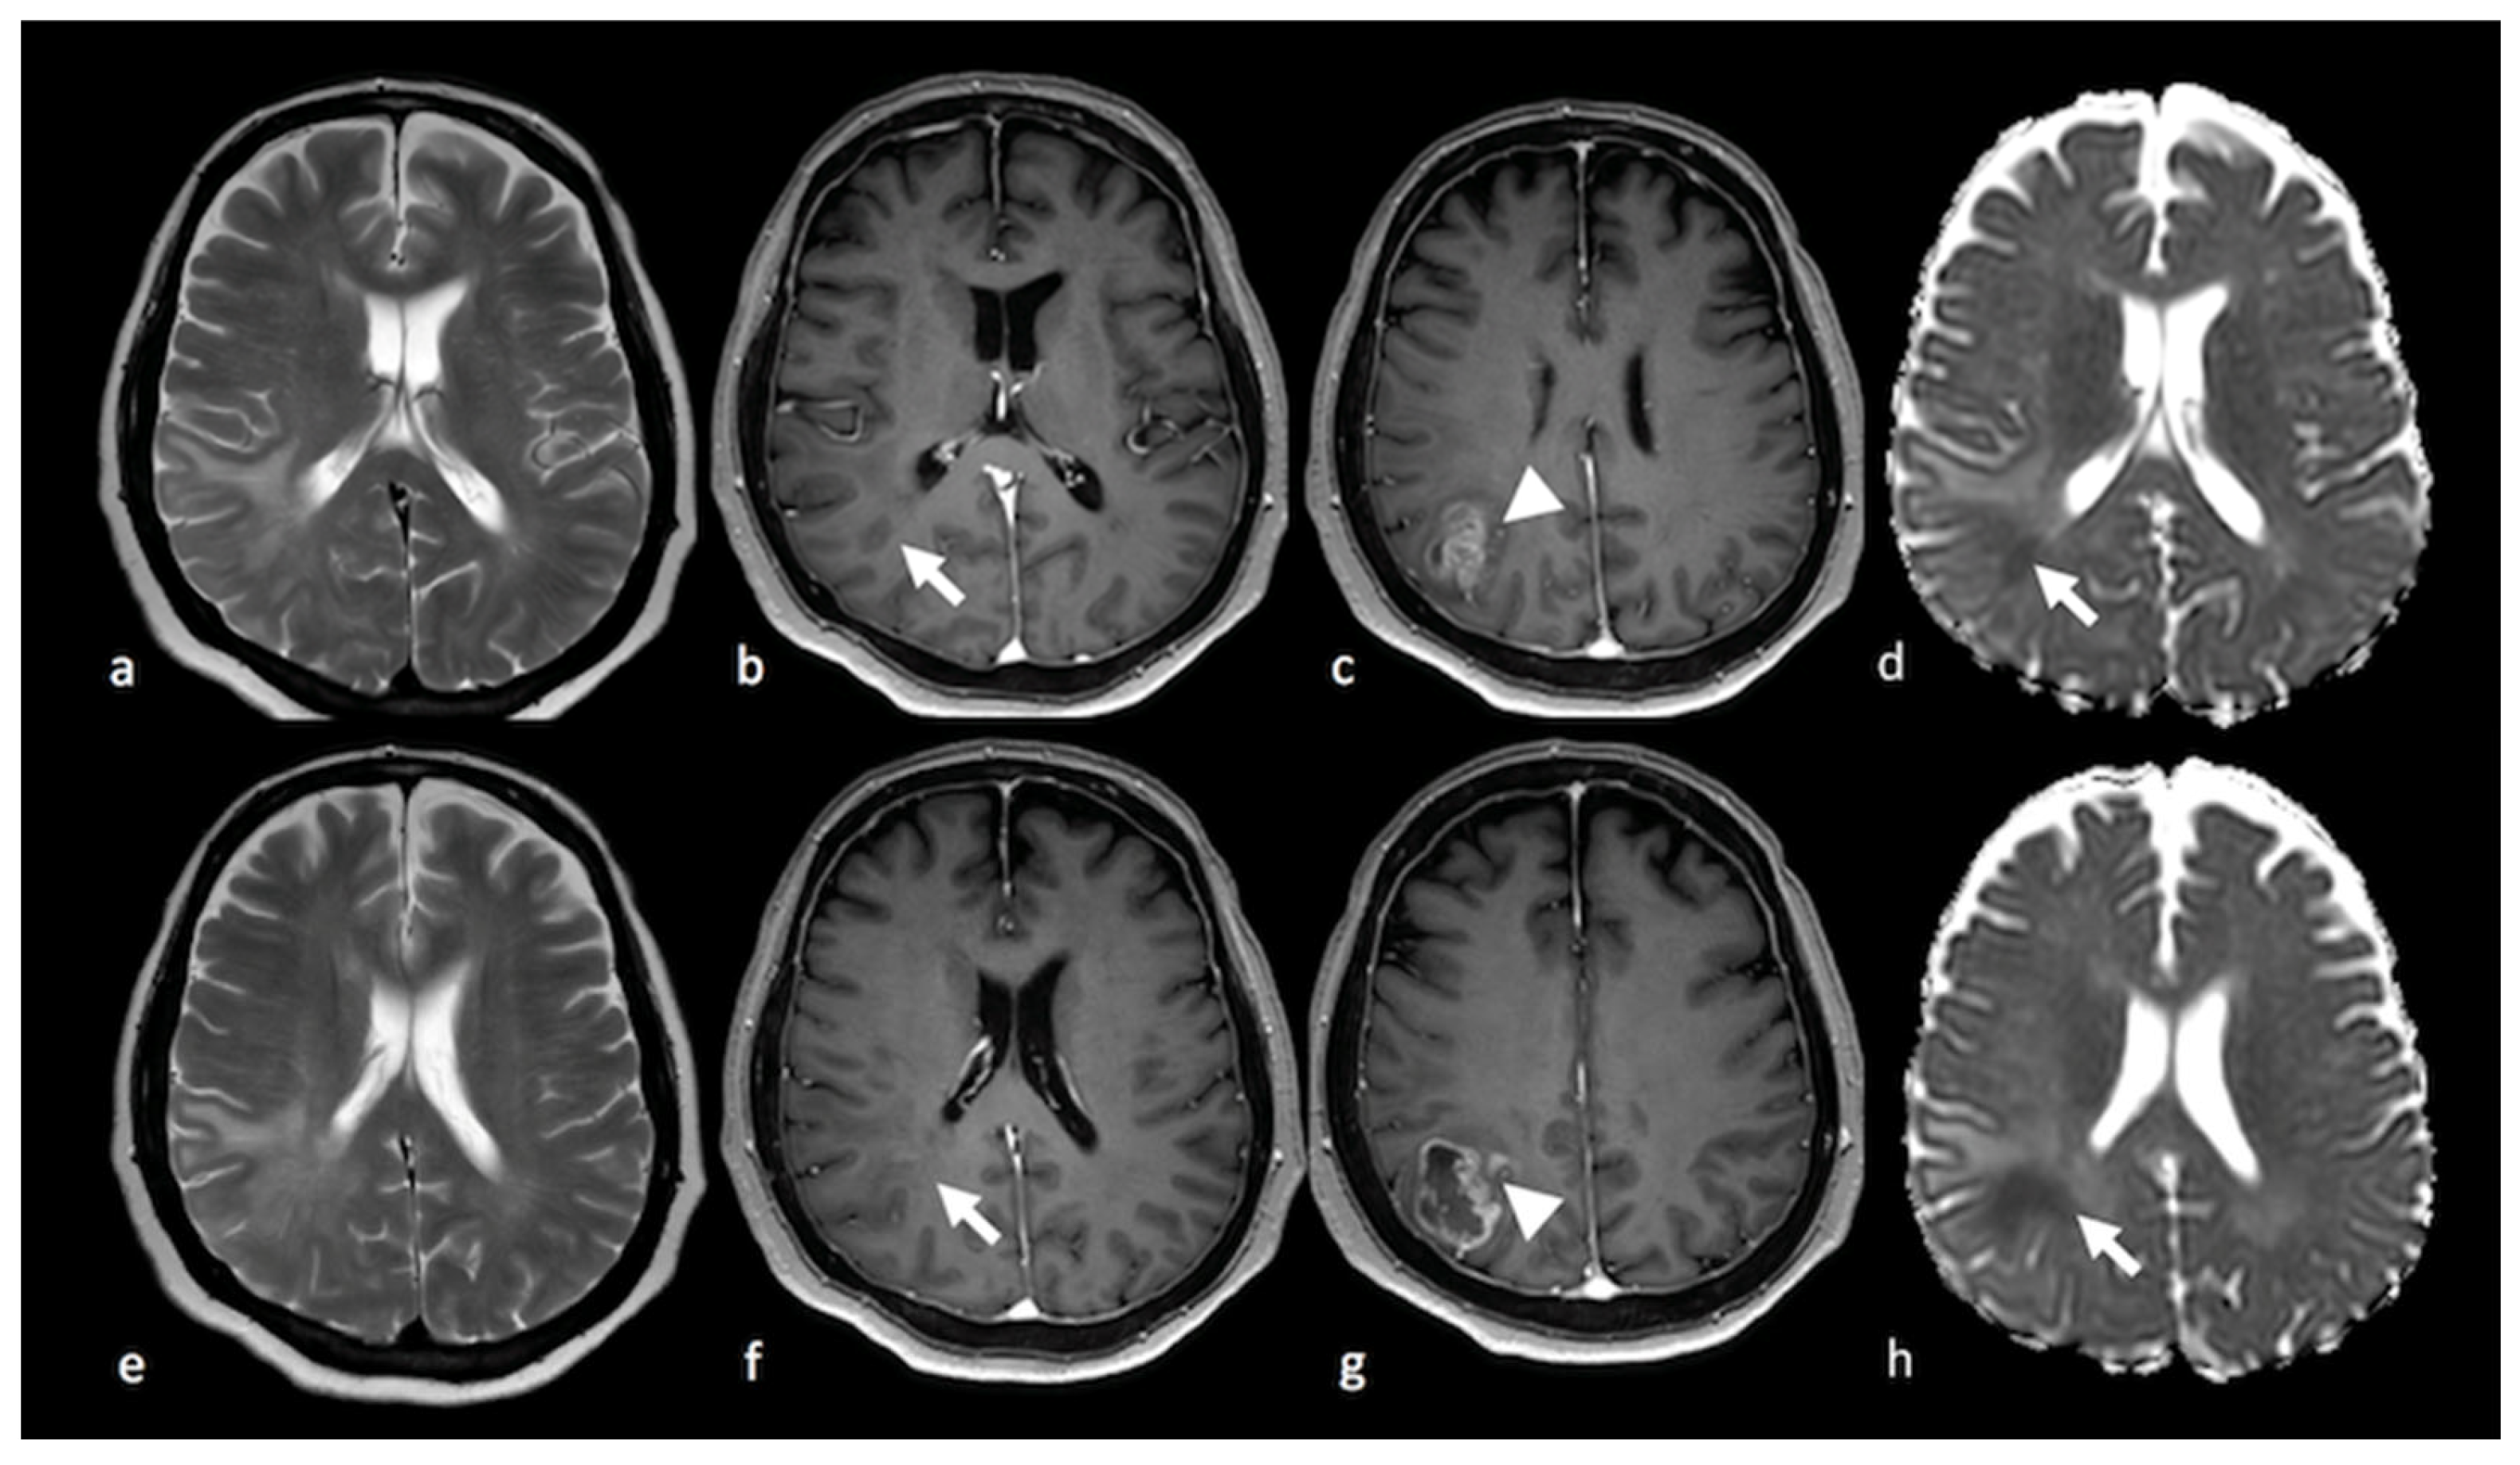

3.1. Conventional MRI

3.2. Diffusion Imaging Techniques

3.2.1. Diffusion-Weighted Imaging (DWI)

3.2.2. Diffusion Tensor Imaging (DTI)